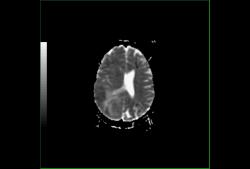

Диффузионная ADC карта